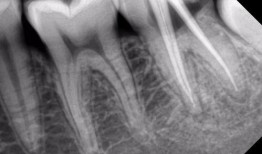

根管治疗视频,从视频学习根管治疗技巧与流程

最近牙疼得我简直要抓狂了!你知道那种感觉吗?就像有一颗小钢珠在你的牙髓里不停地滚动,痛得你连呼吸都小心翼翼。于是,我决定上网搜一...